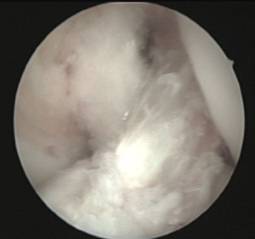

Existeix, així mateix, la possibilitat de lesions parcials del lligament creuat en què només es trobi afectat un dels seus fascicles (anteromedial o posterolateral).

Quan l’afectació determina la presència de simptomatologia clínica s’aconsella la reparació selectiva del fascicle lesionat mitjançant ligamentoplàsties de reforç artroscòpiques preservant les restes de lligament creuat anterior funcionants